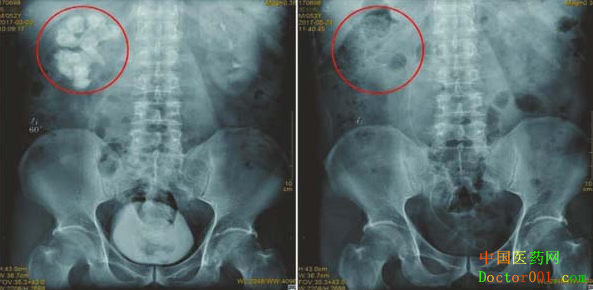

邹先生右肾结石术前与术后X光图

入院后,四川结石病医院的检查结果显示,多年来经历了100多次体外碎石的宋先生,结石不仅没排出去,反而已经长满了右肾,因为结石堵住尿路,导致尿液排不出去,全部堆积在肾脏里,右肾功能现在仅剩下4成左右,而左肾则出现了可怕的肾萎缩。

无独有偶,之前四川结石病医院也诊治过一位来自南充市的患者邹先生,该患者在患上肾结石20年时间里竟然接受了体外碎石达200余次。然而,在他花掉40余万费用后,他的右肾却反而长满了结石,长度达惊人的10厘米;2016年,他几乎每周血尿一次,右肾功能仅剩2成左右……